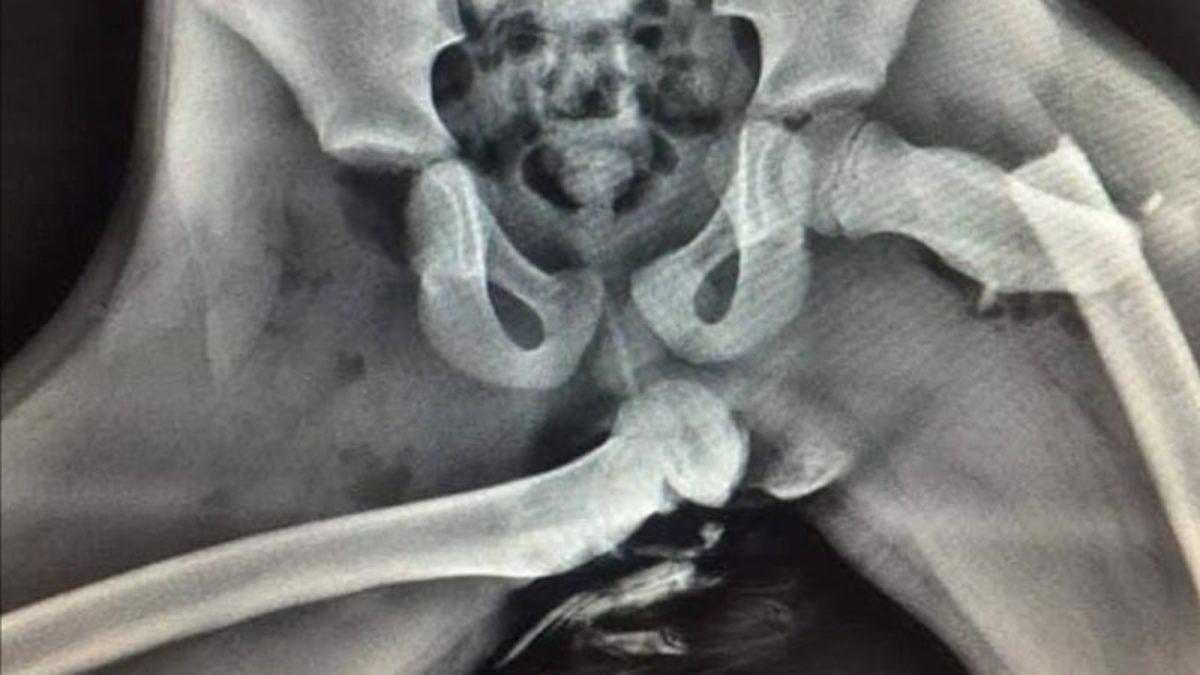

Şimdi de sizlere, tıpkı yukarıdaki gibi otururken hafif bir trafik kazası geçiren bir kazazedenin röntgen görüntülerini aktaracağız. Aracın içerisinde bulunan diğer kişiler, aynı kazadan hafif sıyrıklar ve ufak kırıklarla kurtulurken söz konusu kazazede, diğer yolculardan kat be kat daha ağır yaralandı. Sizlere az sonra aktaracağımız görüntü, ayaklarınızı torpido üzerine koyarken bir kez daha düşündürecek.

İşte o kazazedenin röntgen görüntüsü

Yukarıdaki görüntü, hava yastıklarının açıldığı bir sırada genç bir kızın nasıl ağır yaralandığını açıkça gösteriyor. Ayaklarını torpido üzerine koyarak yolculuk eden genç kız, hava yastıkları açıldığı sırada bacaklarını çekemiyor ve o an ki basıncın etkisiyle kalça kemiğinde kırıklar oluşuyor. Üstelik bir kemiğin olması gereken yerin ne kadar uzağında olduğu da yukarıdaki görüntüde açık bir şekilde görülebiliyor.